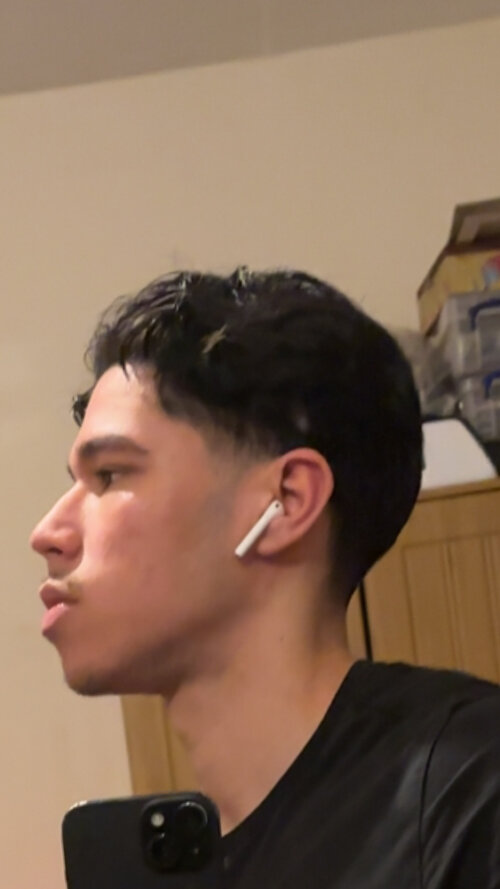

mateus17

6ft recessed LTN

Some dude made this morph of me.

I have a narrow upper jaw so I’m going to see a doctor on the 10th of April to see if I can get a sarpe.

Would a sarpe and then lefort 1 (make my maxilla more prominent) paired with a bimax and genio(fix my lower third) make this morph slightly possible? Ofc I know that it’s impossible to even replicate this morph irl. Just want your thoughts on the direction of procedures that could make it look similar .

I have a narrow upper jaw so I’m going to see a doctor on the 10th of April to see if I can get a sarpe.

Would a sarpe and then lefort 1 (make my maxilla more prominent) paired with a bimax and genio(fix my lower third) make this morph slightly possible? Ofc I know that it’s impossible to even replicate this morph irl. Just want your thoughts on the direction of procedures that could make it look similar .